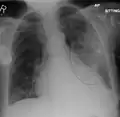

Normal lateral CXR -

AP CXR showing left lower lobe pneumonia associated with a small left sided pleural effusion -